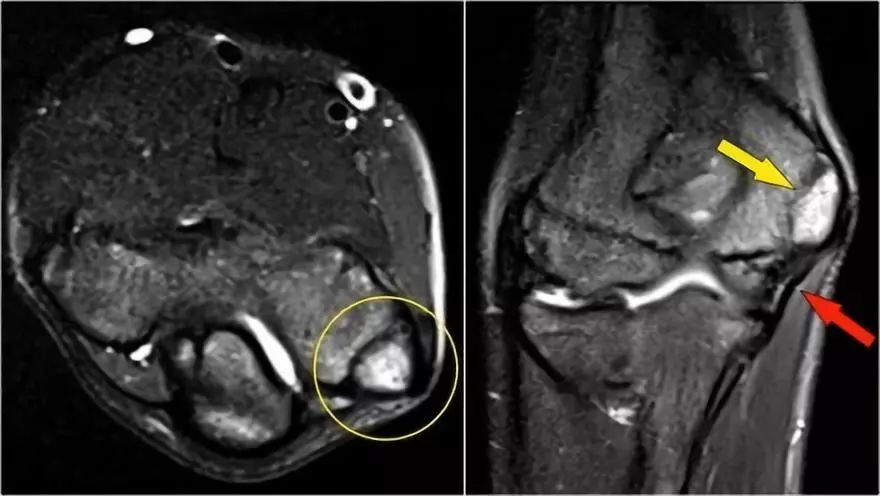

肱骨小头OC病变

慢性过度外翻可导致肘外侧的骨软骨病变。这是重复冲击和剪切力的结果。

下面的射线照片是一名15岁的棒球运动员,有4年的肘部疼痛史以及最近一次锁定。肱骨小头有一个局部透明度区和一些破碎,这是典型的小头骨软骨病变,

这对于头状骨的是典型的,锁定可能是游离体的结果。

MR-关节造影证实了骨软骨病变。在肱骨和骨软骨病变之间存在钆造影剂,这表明它是不稳定的。注意轴向图像上看到的碎片。

肱骨小头的的骨软骨病变常见于投掷和体操运动员(11-15岁),由于负重,他们会出现很多手腕和肘部问题。下面是一个20岁的体操运动员的另一个案例。

同样,射线照片也有透明度区。MR-关节造影显示冠状视图上的一些骨髓水肿。矢状T1W图像显示软骨下骨异常,但片段不多。有一些软骨变薄,但不是缺陷。这显然是一个稳定的片段,没有游离体。

下面这些图像是一名年轻的棒球运动员,在14岁时出现肘部疼痛。T2W-fatsat图像显示骨髓水肿,并且可能存在软骨下骨折。

然而他要继续投掷,因为他三年后在17岁时才来就诊。T1W图像显示碎片(黄色箭头),游离体(红色箭头)。T2W图像表明片段不稳定,因为片段和肱骨之间存在高信号。